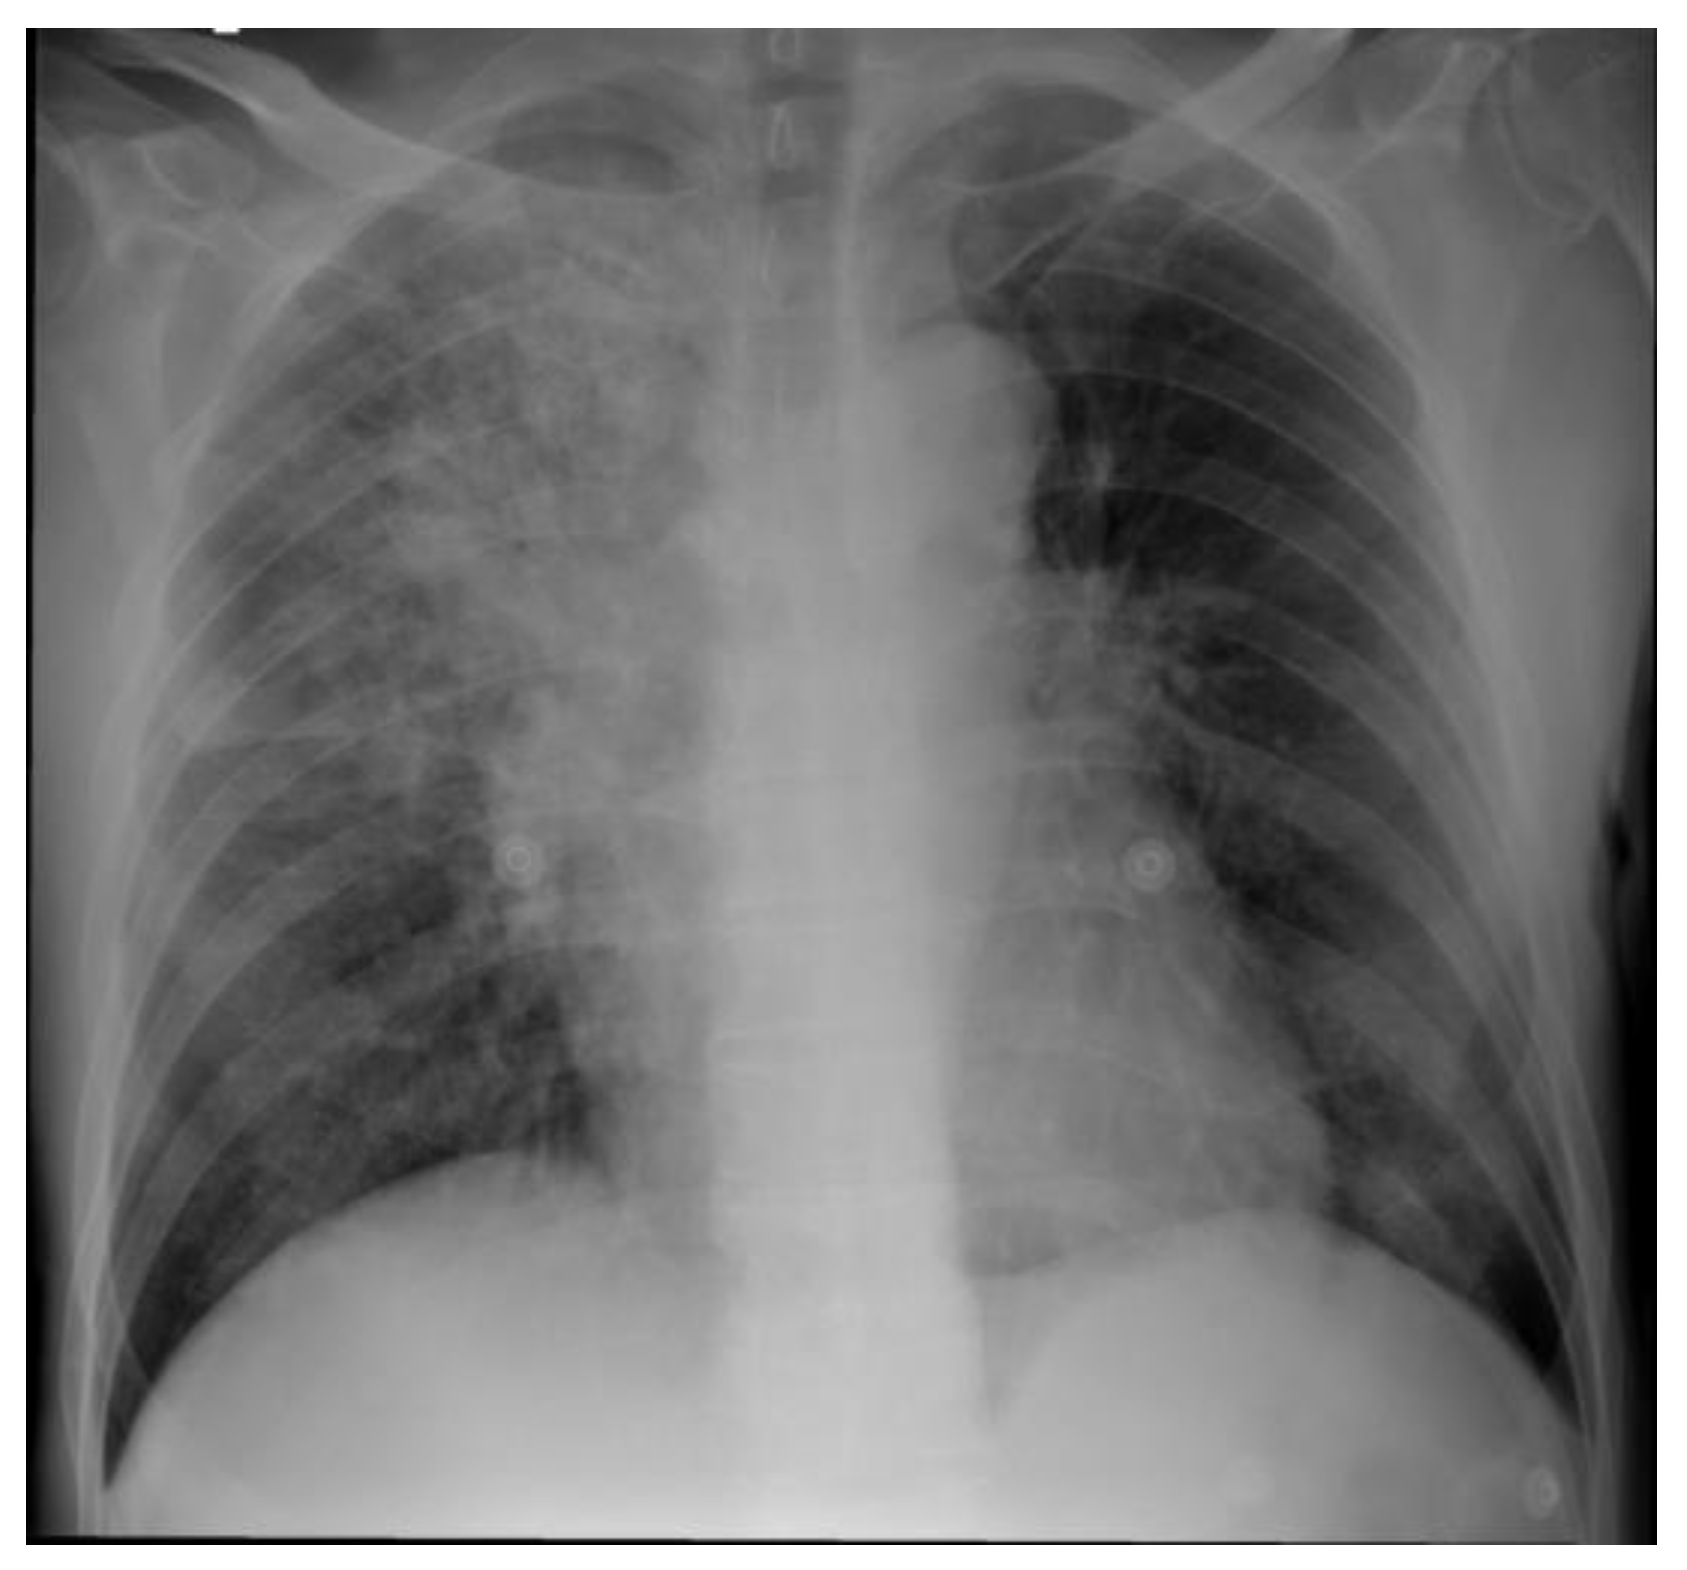

A 63-year-old man, previously healthy and living in a rural area, presented with a 5-month history of hemoptysis, pleuritic pain, weight loss of 14 kilograms, and night sweats. One month before admission he had been diagnosed initially with community-acquired pneumonia at his local hospital however, no information about the treatment was available. At admission, the patient was in poor general condition with tachycardia, fever, and tachypnea. Physical examination revealed no abnormalities in the cardiopulmonary and skin exam. The initial investigation showed a high C-reactive protein (10.74 mg/dL; reference range: 0-0.3 mg/dL), leukocytosis (21,800/mm3; reference range: 5,000-10,000/mm3), neutrophilia (19,900/mm3; reference range: 4,000-7,000/mm3), and a chest X-ray with parenchymal consolidation in the right upper lobe and poorly defined opacities in the middle lobe (Figure 1). A contrasted computed tomography scan of the chest showed extensive pulmonary parenchymal involvement in the right upper lobe and middle lobe and an anterior mediastinal mass with central necrosis and enhancement of its contours (Figure 2).

Figure 1. Chest radiograph. A posteroanterior view revealed consolidation in the right superior lobe and poorly defined opacities in the middle lobe.